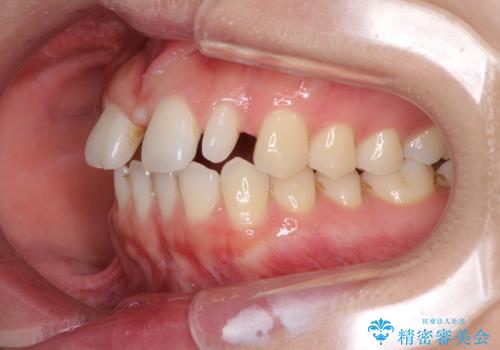

欠損歯と矮小歯 矯正治療と前歯のセラミック治療

- 前歯の隙間を気にして来院された患者様です。

診察の結果、前歯が1本欠損しており、さらに矮小歯(通常よりも小さい歯)が1本存在していました。

欠損による前歯のスペースが大きかったため、事前にワイヤー矯正で前歯の位置を大きく動かし、その後は上下をインビザラインで整えることとしました。

矯正治療後には欠損部はオールセラミックブリッジに、矮小歯はオールセラミッククラウンにて補綴することとしました。

前歯のスペースは、堅い線維の通った歯肉があり、幅も大きかったことから、歯肉切除を行った上でワイヤー矯正により移動を行いました。また、上唇小帯も歯間部付近まで付着していたため、合わせて切除しました。

ワイヤー矯正により、インビザラインよりも早く、歯軸の向きもコントロールしながら移動させることができました。